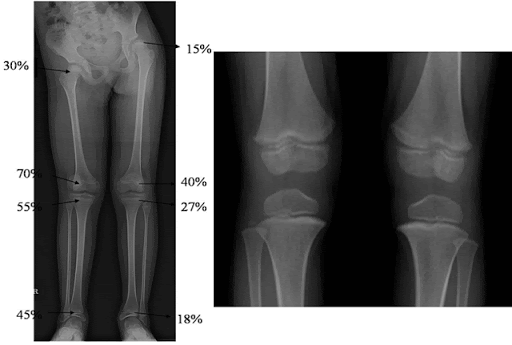

각 장골 기준으로 보면

대퇴부위는 근위/원위 3:7 비율로

비골의 경우 근위/원위 6:4 비율로

경골의 경우 근위/원위 5.5:4.5 비율로 성장하게 됩니다.

(슬관절에서 길이성장이 많이 일어납니다.)

하지 전체로 보았을 때에는 총 100%라고 보았을 때 대퇴근위15%/대퇴원위40%/경골근위27%/경골원위18% 로

대퇴뼈에서 길이성장을 더 많이 하는 것을 알 수 있습니다.